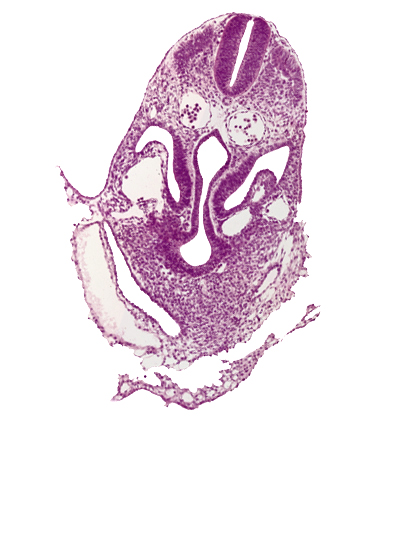

Carnegie Embryo #8943 | Location: 05-03-01

Keywords: amnion, amniotic cavity, dermatomyotome 6 (C-2), dorsal aorta, hepatic antrum, junction of left horn of sinus venosus and left umbilical vein, left umbilical vein, midgut, pericardial cavity, peritoneal cavity, postcardinal vein, right horn of sinus venosus, umbilical vesicle wall, ventral body wall

Source: The Virtual Human Embryo.